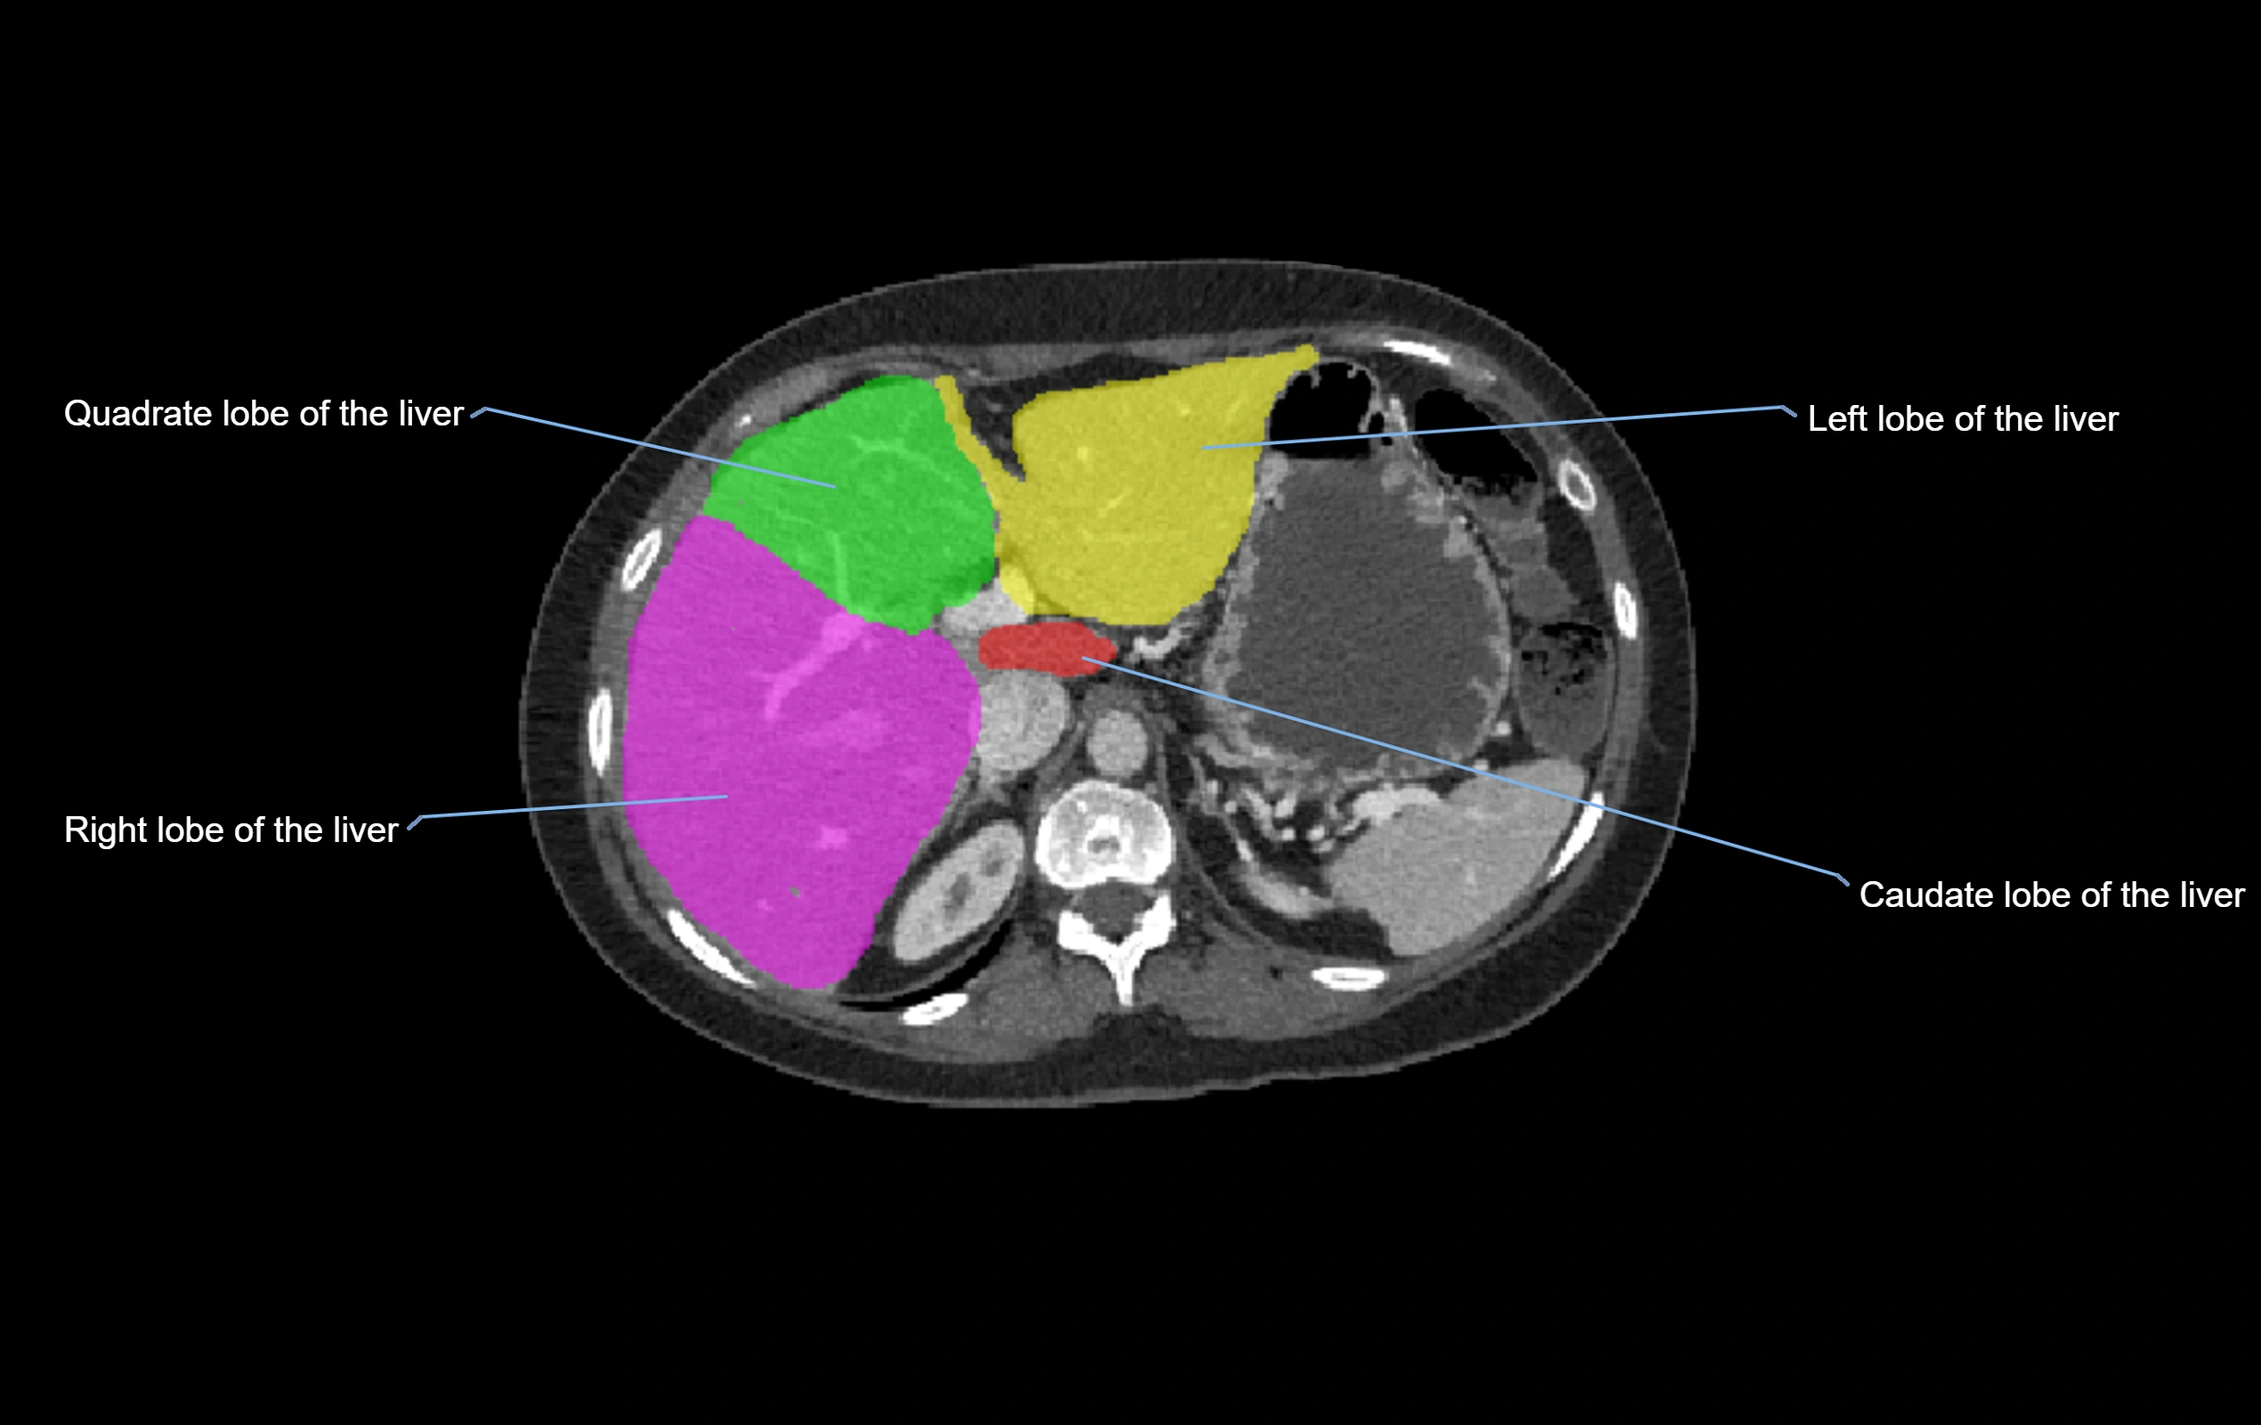

The caudate lobe of the liver is a distinct anatomical subdivision of the liver, designated as segment I in Couinaud’s classification. It lies on the posterior surface of the liver, between the fissure for the ligamentum venosum (left boundary) and the groove for the inferior vena cava (IVC) (right boundary). Superiorly, it is related to the posterior liver surface, and inferiorly it is separated from the left lobe by the porta hepatis.

The caudate lobe is unique because it receives dual portal venous and arterial inflow from both the right and left portal veins and hepatic arteries. It also has independent venous drainage directly into the IVC via multiple small hepatic veins, unlike other lobes that drain through the three main hepatic veins.

This anatomical autonomy makes the caudate lobe especially significant in liver surgery, transplantation, and hepatic venous outflow obstruction syndromes (e.g., Budd–Chiari syndrome). Enlargement of the caudate lobe is a characteristic imaging feature in chronic liver disease and cirrhosis.

CT Appearance

CT Pre-Contrast:

• Caudate lobe appears as a soft-tissue density, isodense to the rest of the liver

• Enlargement may be appreciated in cirrhosis or Budd–Chiari syndrome

CT Post-Contrast:

• Homogeneous enhancement in the portal venous phase, similar to rest of liver

• Independent venous drainage into the IVC may be visualized

• Lesions follow characteristic CT enhancement patterns (HCC: arterial hyperenhancement with washout; hemangiomas: peripheral nodular enhancement with centripetal fill-in)

CT Venous Phase (functional significance):

• Caudate lobe often enhances relatively more than other lobes in Budd–Chiari syndrome, due to preserved venous outflow